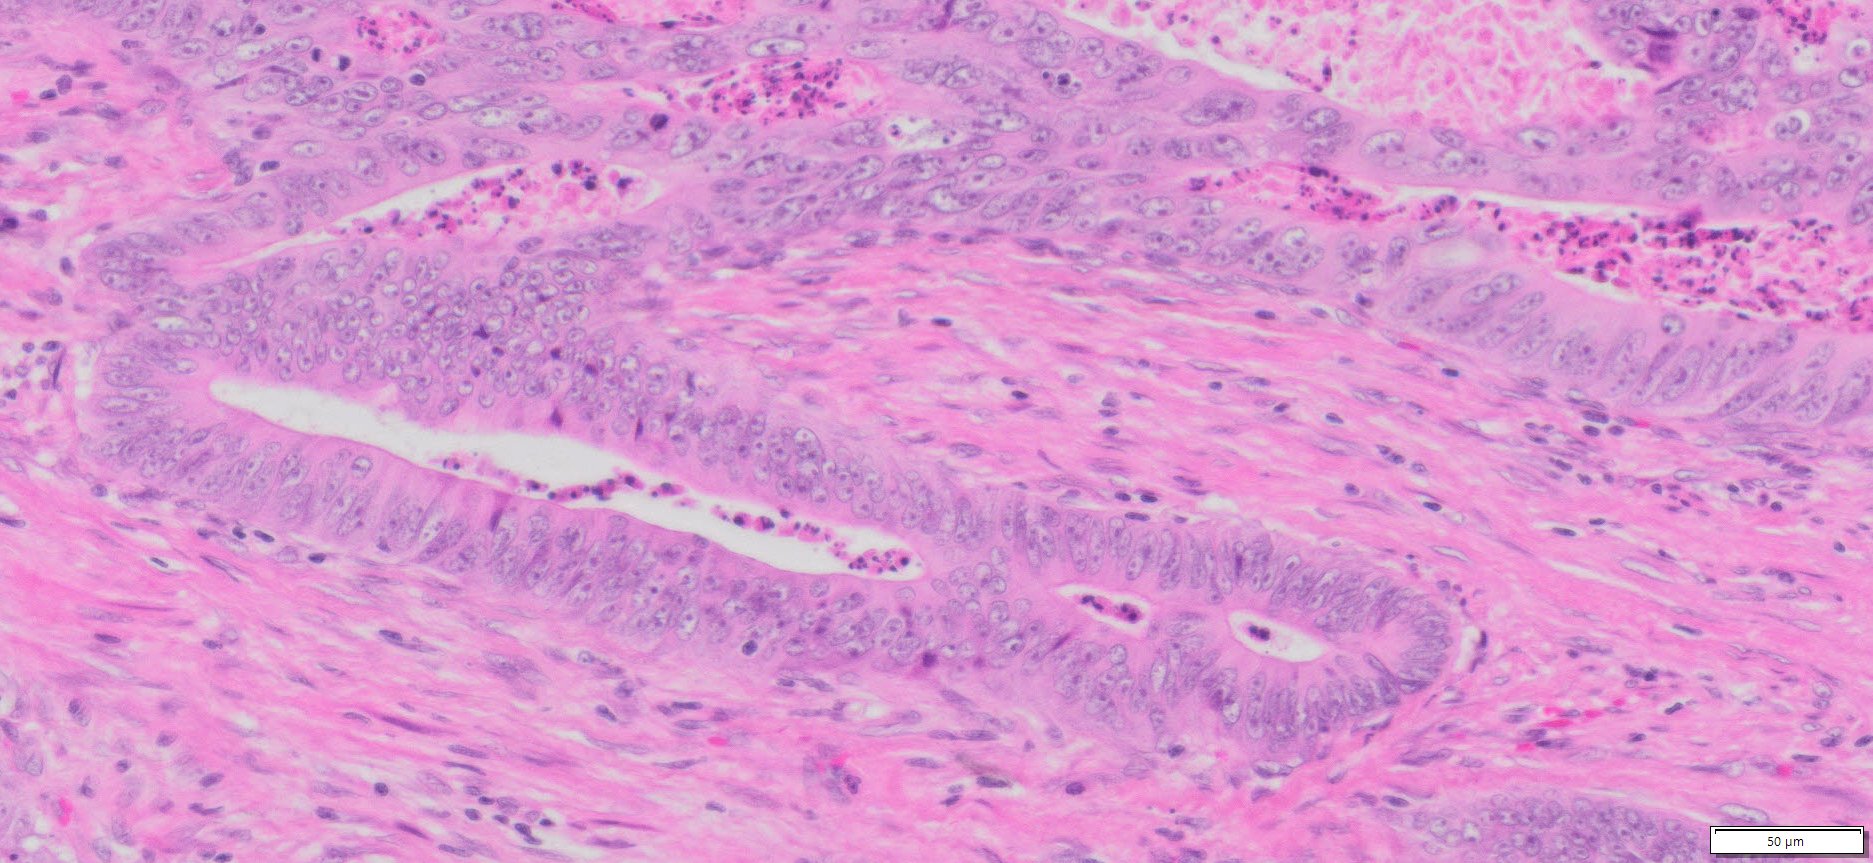

Description

| Tissue | Pathology Diagnosis | Gender/Age (year) | % Tumor area | Tumor Grade | TMN Stage | IHC Data |

| HumanRectum | Moderately differentiated adenocarcinoma of the Rectuma | Female/59 | 45% | II | pT3pN1bpMx | MLH-1,MSH-2,MSH-6 and PMS-2: Preserved nuclear Staining |

Images for H&E Stain and IHC